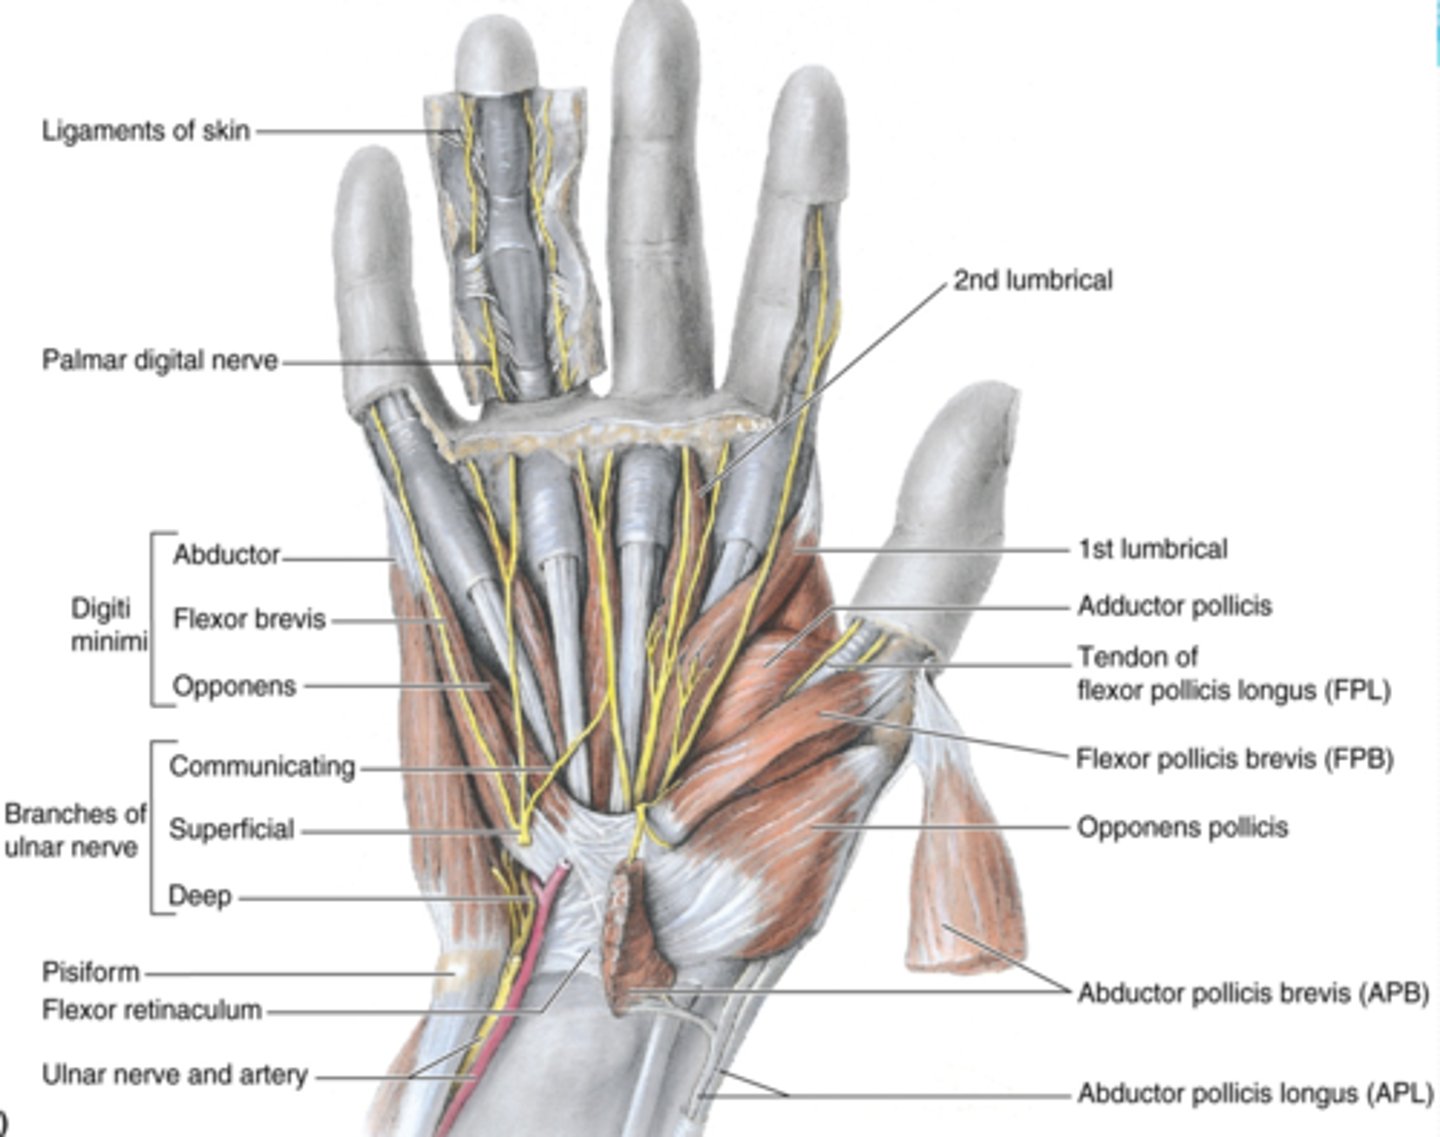

(Muscles of hand:) Muscles of thenar eminence

These muscles are responsible for opposition of thumb

-Abductor pollicis brevis (APB)

-Flexor pollicis brevis (FPB)

-Opponens pollicis

-Abductor digiti minimi

-Flexor digiti minimi

-Opponens digiti minimi

(Muscles of thenar eminence:) Abductor pollicis brevis (APB)

-Abducts 1st digit (thumb), helps opposition

-Median n. (C5 - T1)

-Forms anterolateral part of thenar eminence

(Muscles of thenar eminence:) Flexor pollicis brevis (FPB)

-Flexes 1st digit (thumb)

-Median n. (C5 - T1)

-Medial to APB

(Muscles of thenar eminence:) Opponens pollicis

-Opposes 1st digit (thumb)

-Median n. (C5 - T1)

-Deep to APB

(Muscles of thenar eminence:) Abductor digiti minimi

-Abducts 5th digit

-Ulnar n. (C7 - T1)

-Most superficial of the hypothenar muscles

(Muscles of thenar eminence:) Flexor digiti minimi

-Flexes 5th digit

-Ulnar n. (C7 - T1)

-Lateral to abductor digiti minimi

(Muscles of thenar eminence:) Opponens digiti minimi

-Rotates 5th digit bringing it into opposition with the thumb

-Ulnar n. (C7 - T1)

-Deep to abductor and flexor digiti minimi muscles

Short muscles of hand

lumbricals, dorsal interossei (4) , palmar interossei (3)

(Short muscles of hand:) Lumbricals

-Flex fingers at metacarpophalangeal joints and extend interphalangeal joints of 2nd - 5th digits

-Median n. (C5 - T1)

(Short muscles of hand:) Dorsal interossei (4)

-Abduct fingers

-Ulnar n. (C7 - T1)

-Between the metacarpal bones

(Short muscles of hand:) Palmar interossei (3)

-Adduct fingers

-Ulnar n. (C7 - T1)

-On the palmar surface of metacarpal